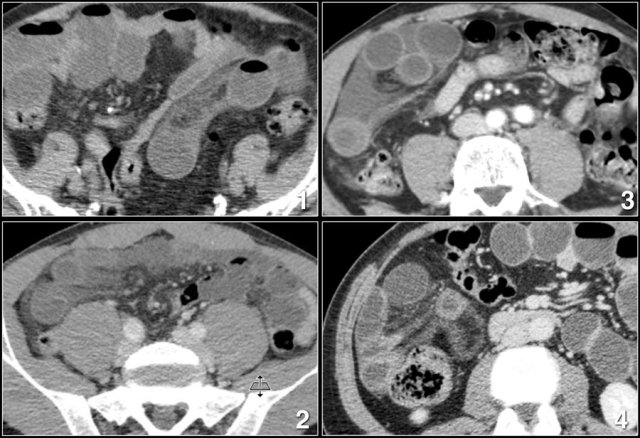

Here the axial and coronal CT images.

Closed loop obstruction is hard to diagnose on CT because it looks like a simple obstruction caused by an adhesion.

You look for a change in caliber of the bowel and once you have found it, you think that the job is done.

Look for an odd position of a group of small bowel loops with mesenteric edema and go for the second obstruction.

The video of the coronal reconstructions better shows the closed loop as well as the two points of obstruction in one plane.

Odd configuration of small bowel loops in patients with a closed loop obstruction Odd configuration of small bowel loops in patients with a closed loop obstruction

Odd configuration of small bowel loops

Look for a strange configuration of small bowel loops clumped together.

Sometimes it looks like a volvulus.

Mesenteric edema Mesenteric edema

Mesenteric edema

Mesenteric edema is the result of venous obstruction due to strangulation.

It is only seen on the mesenteric side of the bowel, unlike the circumferential edema in enteritis or Crohn's disease.